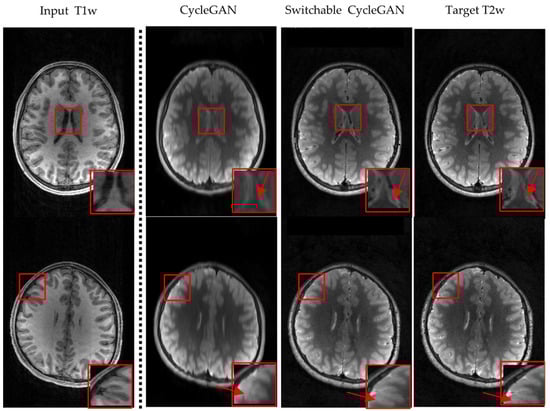

3.2. Visualization